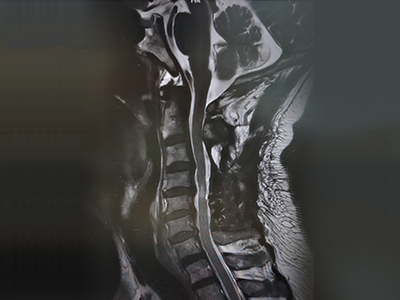

脊柱脊髓神經(jīng)微創(chuàng)中心以微創(chuàng)技術(shù)為引領(lǐng),以功能恢復(fù)為目標(biāo),主要治療脊柱外傷、腫瘤、退行性病變、脊柱畸形等疾病。團(tuán)隊(duì)利用神經(jīng)外科顯微技術(shù),結(jié)合神經(jīng)內(nèi)鏡微創(chuàng)技術(shù),對(duì)脊柱間盤變性疾病、頸腰椎管狹窄、頸腰椎間孔狹窄、頸腰椎間盤突出、頸腰椎體不穩(wěn)、脊柱骨折、寰樞椎脫位、脊柱腫瘤、椎管內(nèi)腫瘤、脊髓損傷、脊髓空洞、脊髓栓系等疾病進(jìn)行高效、特色手術(shù)治療,如顱頸交界區(qū)畸形寰枕減壓內(nèi)固定術(shù)、脊柱腫瘤全脊椎切除內(nèi)固定術(shù)、微創(chuàng)椎管內(nèi)腫瘤切除術(shù)、微創(chuàng)脊柱旁腫瘤切除術(shù)、寰樞椎脫位椎間融合內(nèi)固定術(shù)、脊柱骨折微創(chuàng)經(jīng)皮椎弓根釘內(nèi)固定術(shù)、經(jīng)椎間孔椎間融合內(nèi)固定術(shù)(MIS—TLIF)等,最大程度降低脊柱脊髓手術(shù)創(chuàng)傷,具有創(chuàng)傷小、輸血少、恢復(fù)快、口碑好,出院早等優(yōu)勢(shì)。